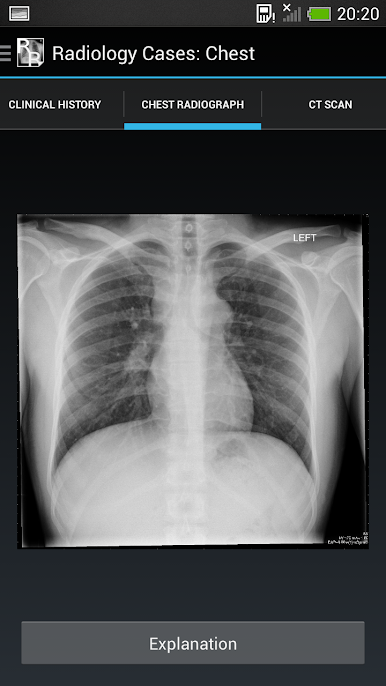

It consists of 26 cases, each with a brief history and a chest x-ray. The user should try to interpret each chest x-ray before revealing the explanations at the bottom of each page.

The aim is to gain an understanding of the basic principles of chest x-ray interpretation and specific radiographic features of common diseases. The diseases encountered are discussed along the way and many of the cases have a scrollable

CT to help with understanding the chest x-ray appearances.